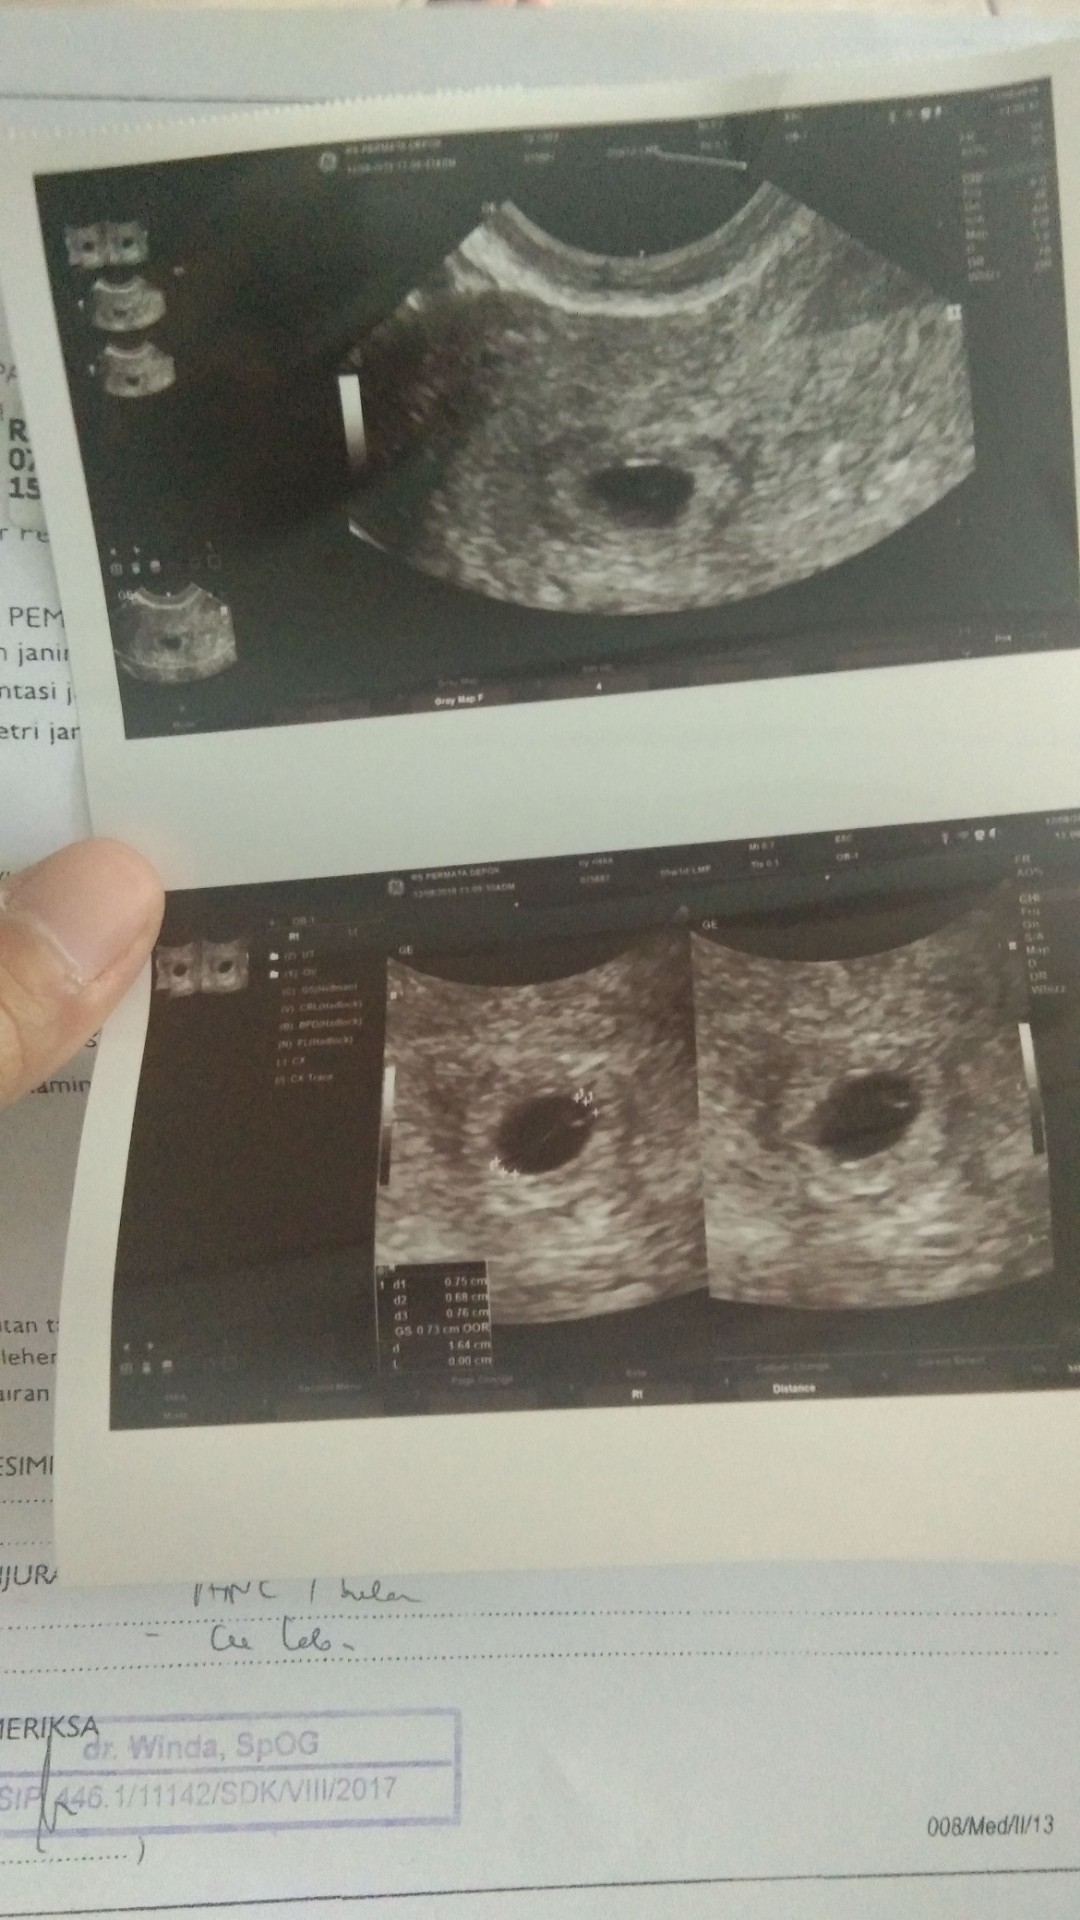

ini USG saya 5week 1day USG lewat transvaginal .